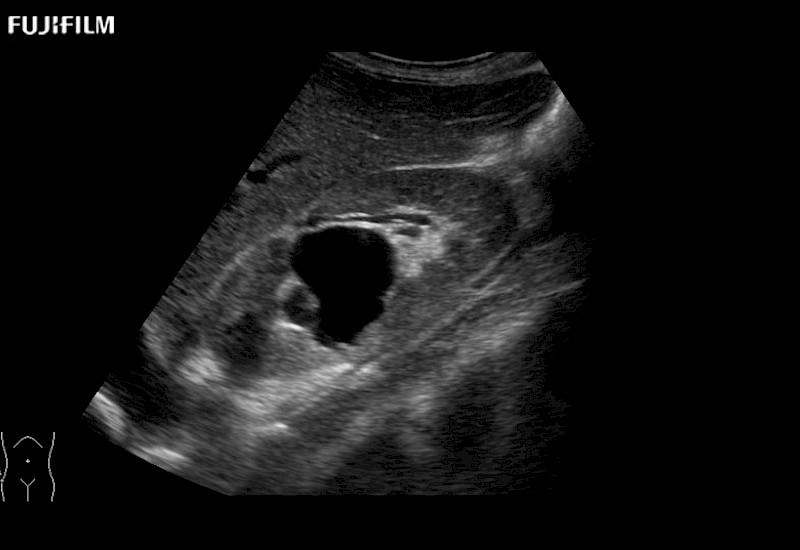

Extraordinary high-resolution digital imaging

Multi-Parametric imaging modalities

- Instant feedback on tumor margin delineation

- Instant feedback on tumor margin delineation

- Instant feedback on tumor margin delineation